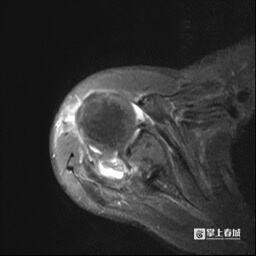

术前影像

面临这一贫乏,甘煜东群众团队谛视分析了妥大爷的病情,聚首影像学查验(MRI)限度,确诊他为弘远不可建筑肩袖挫伤,冈上肌、冈下肌及肩胛下肌腱均扯破彰着。

甘煜东觉得,患者的冈上肌肌腱回缩及脂肪浸润严重,无法建筑。决定经受由我国瓦解医学群众陈世益证据创始的“Chinese-Way”肩要津镜转换性手术神色,该本领由我国始创,获取外洋等闲认同。